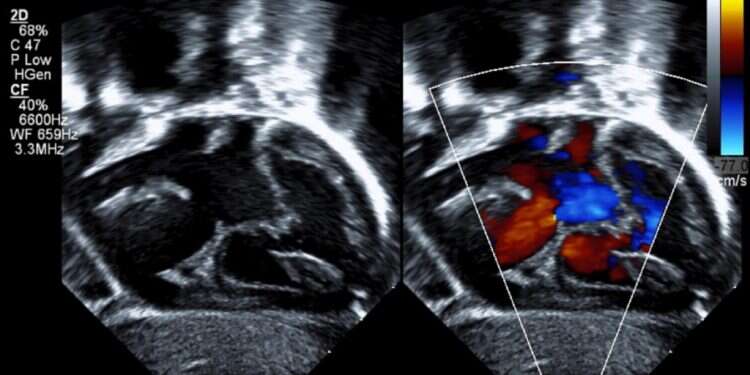

"מומי לב מולדים הם המומים השכיחים ביותר מבין כלל המומים המולדים", מסביר ד"ר תא־שמע. לדבריו, הם מתגלים באחוז אחד מכלל הלידות בעולם. כרבע ממומי הלב המולדים הם קשים ומצריכים התערבות: ניתוח או צנתור, שימוש בתרופות ומעקב לכל אורך חיי המטופל. "עבודתנו כרופאים היא לטפל בילדים שסובלים מן המומים האלו, ובנוסף לגלות את הגורמים הגנטיים שגרמו למחלה ולנסות לסייע בהפחתת שכיחותם".